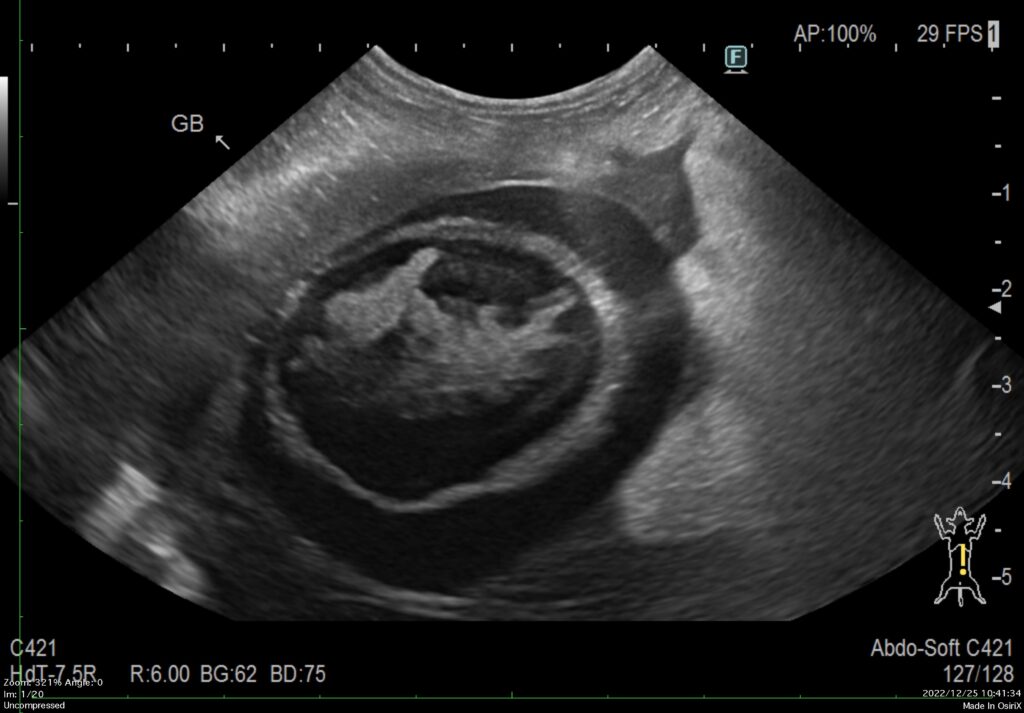

超音波検査では、腫大した膵臓と膵臓周囲の腸間膜の輝度亢進、膵管の拡張、腹水など診断に有用な所見が得られます。報告では、犬の急性膵炎の68%で超音波検査の異常があると示されています。